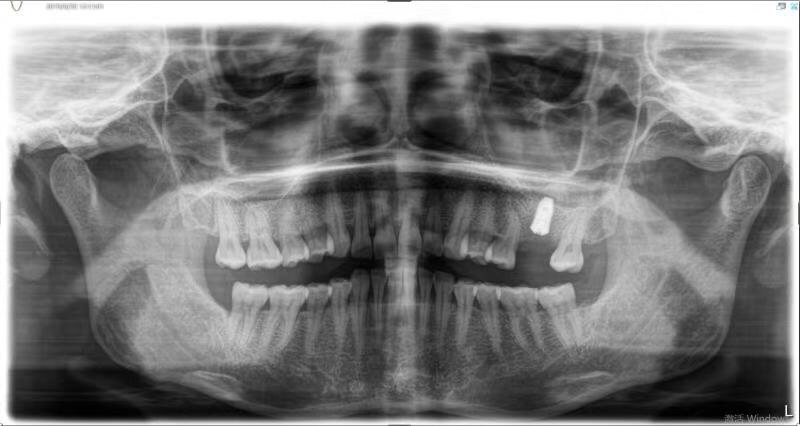

患者中年女性,左上6号牙因根尖炎症过大导致松动后拔除,因炎症过大,稳妥起见未进行即拔即种的种植方式,我们采取了先拔牙,3个月后种植的治疗方案。

由于骨量不足,我们术中进行了上颌窦内提、植骨、盖膜、CGF覆盖,最大程度的保证了种植的成功率和使用强度。